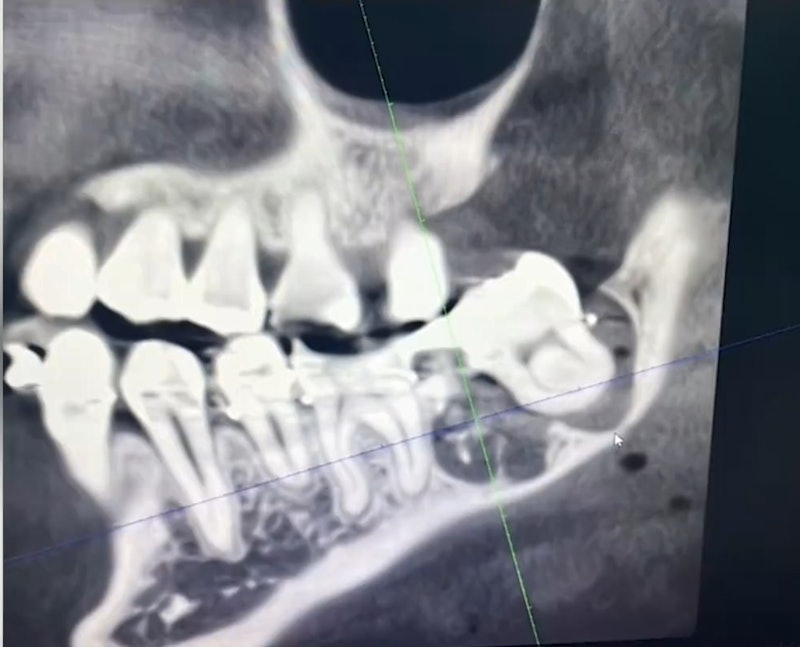

Bệnh viện An Khánh (An Huy, Trung Quốc) đang là tâm điểm của dư luận sau cái chết thương tâm của một phụ nữ 34 tuổi. Nạn nhân đã nhảy lầu tự tử từ tầng 11 của bệnh viện vào ngày 17/3, sau 5 ngày chịu đựng đau đớn tột cùng vì bị nhổ nhầm răng.

Theo lời kể của anh trai nạn nhân trên mạng xã hội, người phụ nữ này đã đến khoa răng hàm mặt của Bệnh viện An Khánh để nhổ răng khôn vào ngày 12/3. Tuy nhiên, bác sĩ đã nhổ nhầm một chiếc răng nguyên vẹn khác, sau đó lại nhét chiếc răng vừa nhổ nhầm trở lại vị trí của răng khôn. Vị bác sĩ này còn tìm cách che giấu sự việc bằng cách sửa đổi bệnh án.

Chồng của nạn nhân cho biết vợ anh đau đến mức mất ngủ, không ăn uống được gì từ khi nhổ răng cho đến lúc qua đời. "Từ khi nhổ răng đến lúc mất, vợ tôi đau đến mất ngủ, không ăn được gì, chỉ uống nước. Khi chúng tôi đến bệnh viện để làm rõ sự việc, bác sĩ liên quan hoàn toàn phủ nhận trách nhiệm", chồng nạn nhân chia sẻ.

Gia đình đã nhiều lần tìm đến bệnh viện để yêu cầu giải quyết nhưng không thành. Phải đến khi nạn nhân chụp phim tại một bệnh viện khác, sự thật mới được phơi bày.